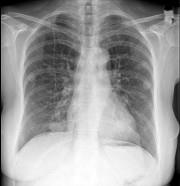

问题 女,51岁,胸闷、咳嗽、咳痰,3年前被确诊为子宫平滑肌肉瘤,请结合胸片选出最可能的诊断()

选项 A.粟粒性肺结核 B.肺转移瘤 C.结节病 D.胶原病 E.真菌病

答案 B